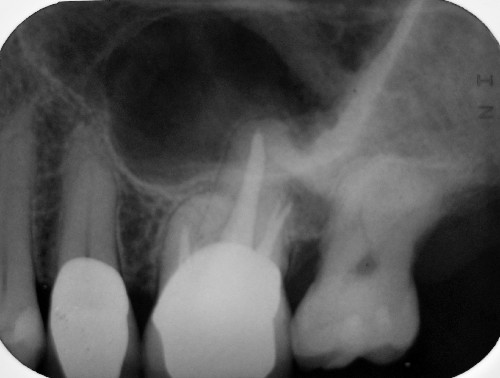

Fall 1:

Exazerbation in 2006 nach WK-Behandlung nach der aktuellen Lehrmeinung (NaOCl, Ca(OH)2) in 2005 (Klick!)